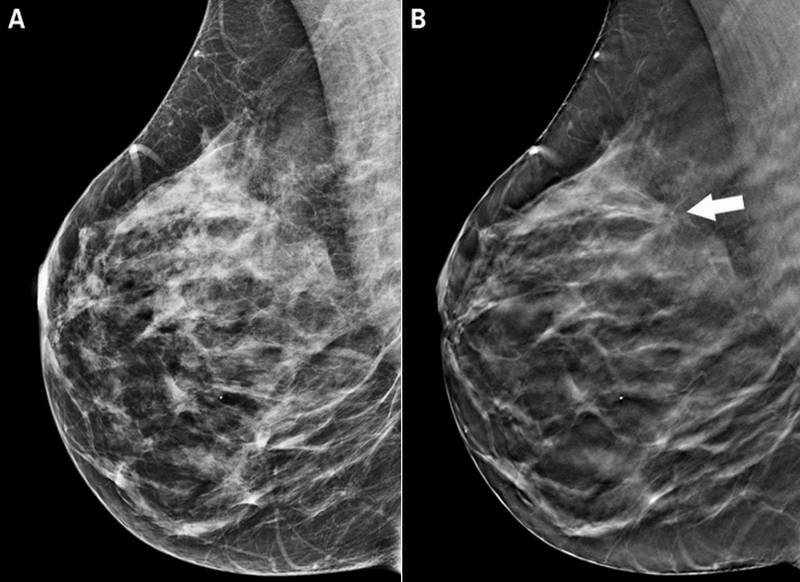

Что такое маммография: важность, процесс и результаты

Раздел: Необычные решения